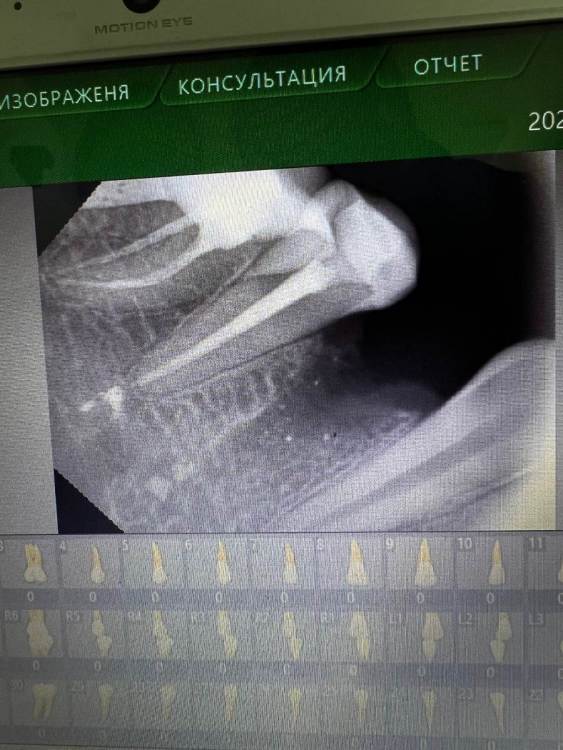

kruckovairina Опубликовано 4 июня, 2023 Поделиться Опубликовано 4 июня, 2023 Удалили 2 зуба по причине кисты (болела , обострилась, не получилось вылечить), и второй зуб , была боль в незалеченном канале , пролечили вывели материал за верхушку корня , болел полтора месяца , не смогла уже терпеть уладила в надежде что все пройдет , но развился альвеолит почистили , положили губку и зашили. , все это очень сильно болело дней 5-7 , были советы закладывать метрогил, все это облегчало на некоторое время , приехала в другой город к другому специалисту снова почистили положили турунду с йодоформом через 5 дней поменяли , и еще 2-3 дня я ходила со второй турундой, все это время все болит , у меня депрессия, мысли уже суицидальные , потому что очень устала , приехала обратно к себе в город пошла на осмотр , вынули турунды и сказали вот теперь точно заживет, полоскать хлорогекседином , раны и правда затягиваются но очень медленно при этом , присутствует боль до сих пор и Жжение сильное , все врачи что смотрели меня говорят терпеть , все пройдет , что визуально все выглядит хорошо !!!!!! За все это время были моменты что поднималась температура до 37,5 сейчас вроде нет , сегодня 10 день после последней чистки , подскажите нормально ли это что все это болит так долго ?????чем себе еще помочь , какие то физио процедуры ? Что я еще могу сделать , очень прошу помогите на нижней лунке на снимке будто остался материал , но его попытались убрать и получается ковыряли уже вместе с днем удаления 3 раза , даже машинкой сверлили , но вот сегодня болит больше верхняя лунка ее прям жжет , может быть слишком много хлорогекседина, мне кажется что динамика есть , но она очень медленная и слабая ?????я очень сильно депрессую и плачу много , не справляюсь .Просто скажите что это болит долгооооооо, и что это нормально , пока не закроетья ранка Ссылка на комментарий

Irouil Опубликовано 4 июня, 2023 Поделиться Опубликовано 4 июня, 2023 Снимки и фотографии выглядят нормально. Чем больше раз чистить заживающую костную рану, тем больше она будет болеть. Метрогил - хорошее средство для первых дней течения альвеолита, сейчас я уже не думаю, что он будет эффективен. Хлоргексидин лучше больше 7 дней не использовать, можно спровоцировать дисбактериоз, я бы рекомендовал попробовать пополоскать растворами для болей в горле (Гексорал, Бросгексин и т.п.) - они имеют слабый анестетический эффект, возможно это улучшит Ваше самочувствие. Ссылка на комментарий